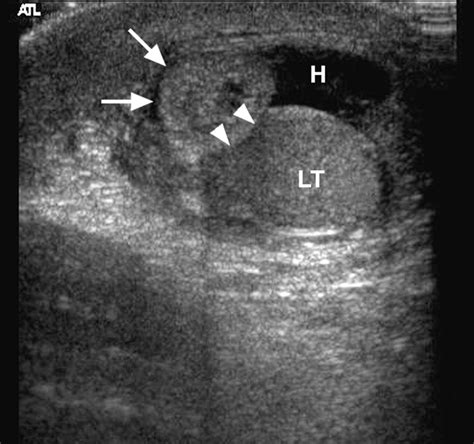

Color Doppler Ultrasound is particularly vital. It allows the radiologist to visualize the blood flow within the affected testicle. If the testicle itself shows normal blood flow but a small, hypoechoic or hyperechoic area is visible at the upper pole, it strongly supports the diagnosis of a torted appendix testis rather than testicular torsion.